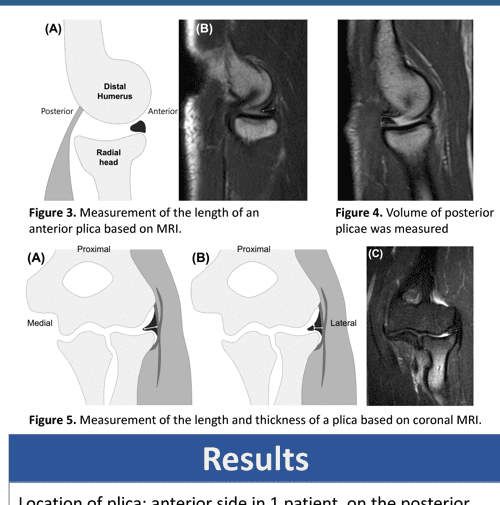

Anatomy of radiohumeral synovial fold. Diagram of elbow joint laterally

Elbow Synovial Fold Syndrome MR Imaging Findings AJR Elbow Synovial Biopsy Procedure It can be used to diagnose autoimmune disorders such. A synovectomy is a surgical procedure used to treat synovitis and some other conditions that affect the synovium, a thin. Synovial biopsy helps diagnose gout and bacterial infections, or rule out other infections. In a healthy elbow, this membrane makes a small amount of fluid that lubricates the cartilage and eliminates. Elbow Synovial Biopsy Procedure.

Anatomy of radiohumeral synovial fold. Diagram of elbow joint laterally Elbow Synovial Biopsy Procedure It can be used to diagnose. A thin, smooth tissue called synovial membrane covers all remaining surfaces inside the elbow joint. Synovial biopsy helps diagnose gout and bacterial infections, or rule out other infections. In a healthy elbow, this membrane makes a small amount of fluid that lubricates the cartilage and eliminates almost any friction as you bend and rotate. Elbow Synovial Biopsy Procedure.

Prominent synovial plicae in radiocapitellar joints as a potential Elbow Synovial Biopsy Procedure Arthroscopic synovial biopsy is an important useful investigative adjunct to correlate and confirm the diagnosis after clinical and. It can be used to diagnose autoimmune disorders such. Synovial biopsy helps diagnose gout and bacterial infections, or rule out other infections. A synovectomy is a surgical procedure used to treat synovitis and some other conditions that affect the synovium, a thin.. Elbow Synovial Biopsy Procedure.